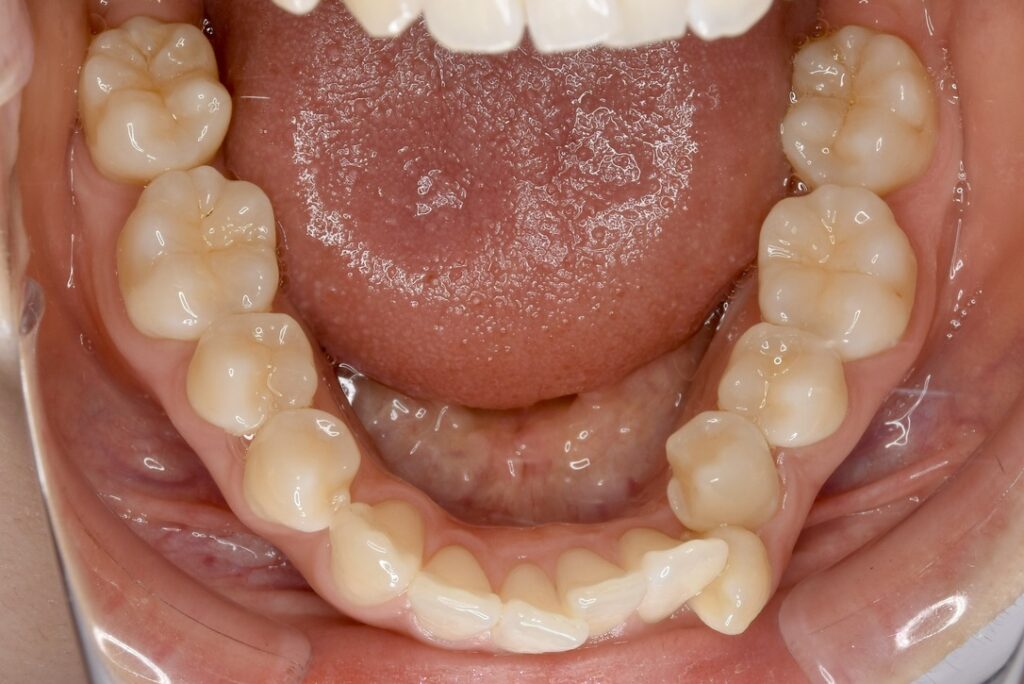

| 主訴 | 写真を見て歯並びが気になる。特に下の前歯はガタガタが強く治したい。 |

|---|---|

| 診断名・主な症状 | 叢生 |

| 年齢 | 19歳 |

| 治療内容 | 上下とも歯並びの幅を広げることでできたスペースを利用して、ガタガタを解消しました。 |

| 使用装置 | 表側矯正(ワイヤー) 矯正用ミニインプラント |

| 抜歯部位 | 抜歯なし |

| 治療期間 | 1年10ヶ月 |

| 通院回数 | 25回 |

| 費用 | 91万円程度(税別) 220 |

| リスク・副作用 | 痛み、歯肉退縮、歯根吸収、抜歯に伴う出血や腫れが生じることがあります。 |